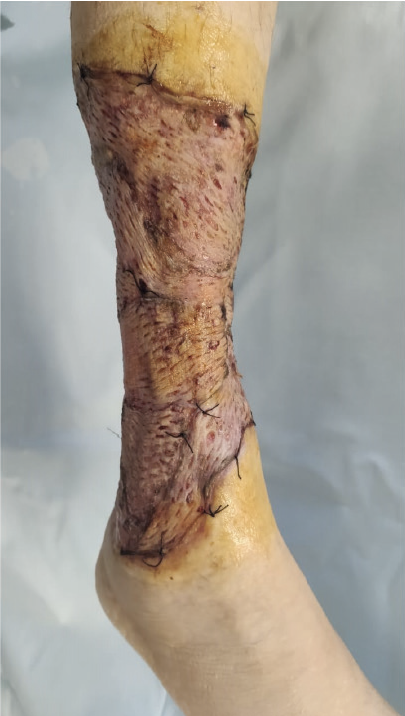

К 16 ноября 2021 г. удалось очистить рану от наложений фибрина, ликвидировать «гнойные карманы», подготовить грануляции к оперативному восстановлению кожного покрова и выполнить аутодермопластику расщепленными перфорированными трансплантатами на площади 1,5% поверхности тела (рис. 4). Терапия на момент трансплантации: метилпреднизолон 40 мг/сут, метронидазол 1000 мг/сут, месалазин 4 г/сут, омепразол 40 мг/сут.

Рис. 4. Состояние после аутодермопластики расщепленными перфорированными трансплантатами (21 ноября 2021 г.)